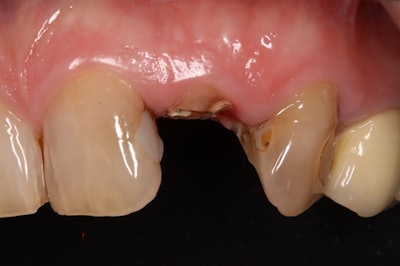

A patient's isogingivally fractured maxillary lateral incisor.Images courtesy of Graf et al. Licensed by CC BY 4.0.